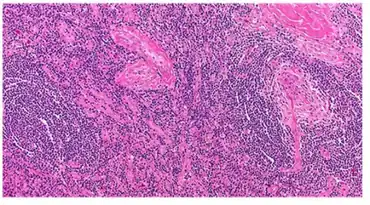

Micrograph of lymph node biopsy demonstrating hyaline vascular features consistent with Castleman disease | |

The microscopic appearance (histology) of biopsied tissue from an enlarged lymph node must demonstrate a constellation of features consistent with Castleman disease. There are three patterns of characteristic histologic features associated with UCD:[5]

- Hyaline vascular - regressed germinal centers, follicular dendritic cell prominence or displasia, hypervascularity in interfollicular regions, sclerotic vessels, prominent mantle zones with an “onion-skin” appearance.

- Plasmacytic – increased number of follicles with large hyperplastic germinal centers and sheetlike plasmacytosis (increased number plasma cells).

- Mixed - features of both hyaline vascular and plasmacytic patterns

UCD most commonly demonstrates hyaline vascular features; however, plasmacytic features or a mixture of both hyaline vascular and plasmacytic features may also be seen in UCD lymph nodes.[4] The clinical utility of subtyping Castleman disease by histologic features is uncertain, as histologic subtypes do not consistently predict disease severity or treatment response.[5]